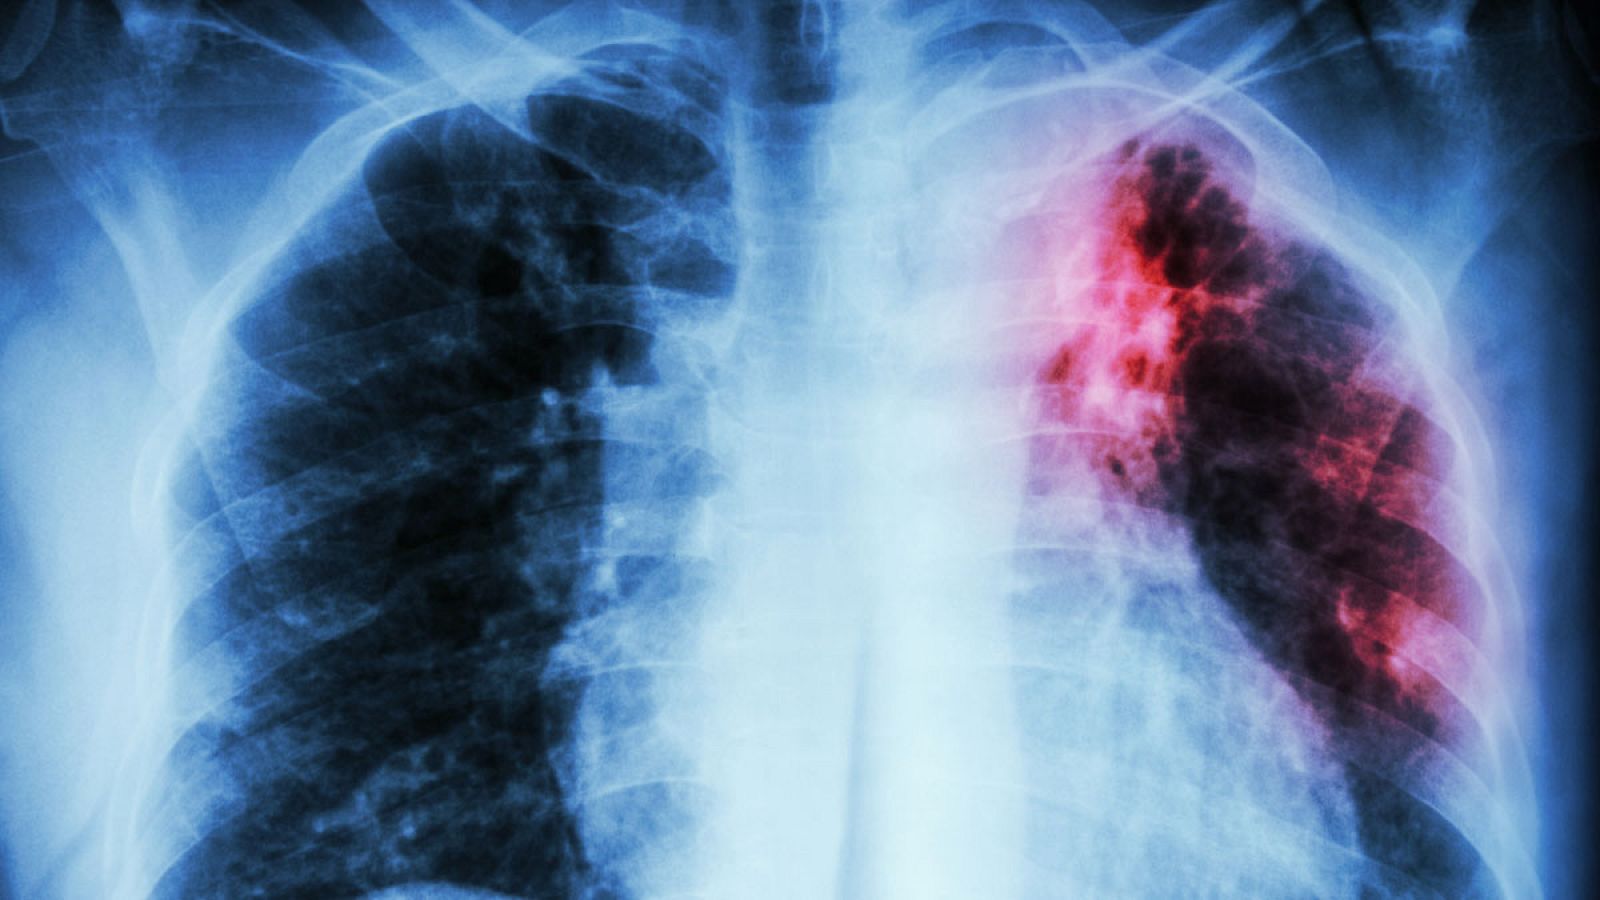

Radiografía de un paciente afectado por tuberculosis.

La tuberculosis sigue siendo la principal causa de muerte infecciosa, responsable de 1,6 millones de muertes en todo el mundo en 2017, con formas de tuberculosis resistentes a los medicamentos que amenazan los esfuerzos por controlarla en muchas partes del mundo. Además, en 2017, alrededor de una cuarta parte de la población mundial vivía con la infección de tuberculosis.